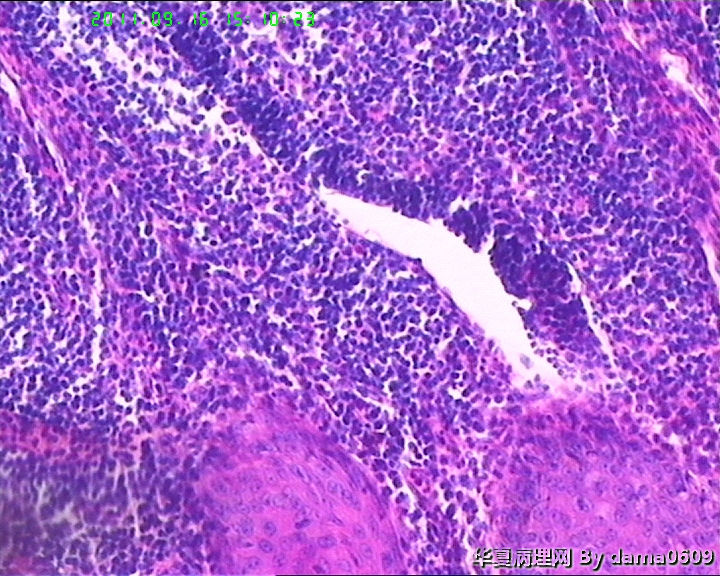

• 背部肿物,急请老师看看!!图3

图3

该患者经上级医院会诊,回报:(背部皮肤)淋巴组织增生,伴轻度异形;鳞状上皮呈乳头状增生,伴轻-中度不典型增生。建议密切随诊。免疫组化结果:CD3(+), CD5(+), CD20(+)部分,CD21(+), CD68(+)部分,Ki67---15%。